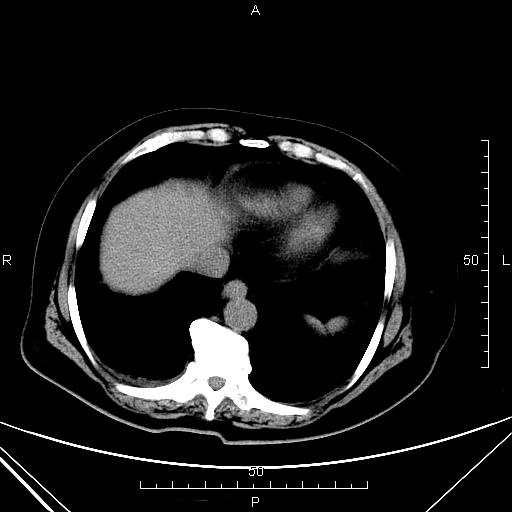

CT49782:上腹部CT

女,68岁,上腹部疼痛3天。

支持胆总管癌。扩张胆总管消失下方(胰腺段稍上方)见圆形结节影,延迟持续强化。

肝门胆管细胞癌。胆总管中断,局部见结节,增强后明显强化,以上肝内胆管扩张。唯一就是肝内胆管扩张程度轻了点。

胆总管胰腺上段(扩张胆总管消失下方层面)内见结节影,延迟强化,符合胆总管癌。

肝内胆管多发扩张,考虑占位不排除,建议MRCP

支持1、胆总管上段结节影伴肝内胆管、左右肝管及肝总管扩张,占位性病变待排,建议MRCP或ERCP;

2、胆囊炎,胆囊结石;

建议MR检查(MRCP),以除外总胆管占位性病变